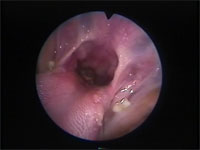

Abb 2 Larynx-schwer-einsehbar

Abbildung 2: Blick in den Pharynx der Katze. Der Kehlkopf ist nur schwer einzusehen.

Katzen sind wegen der Kleinheit ihres Oropharynx nicht immer leicht zu intubieren. Durch die Wölbung der Zungenoberfläche ist die relativ tief liegende Epiglottis nicht immer direkt einsehbar.